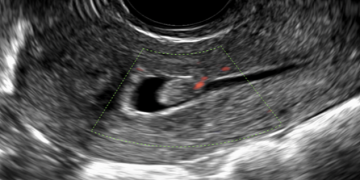

Guida al Counselling di Ottobre 2022: ridotta riserva ovarica e CFA

Cari colleghi, vi presentiamo la guida al counseling di Ottobre relativa alla ridotta riserva ovarica e alla conta dei follicoli antrali!! Potrete scaricarla cliccando sul link. Grazie a Carlotta Zorzi...